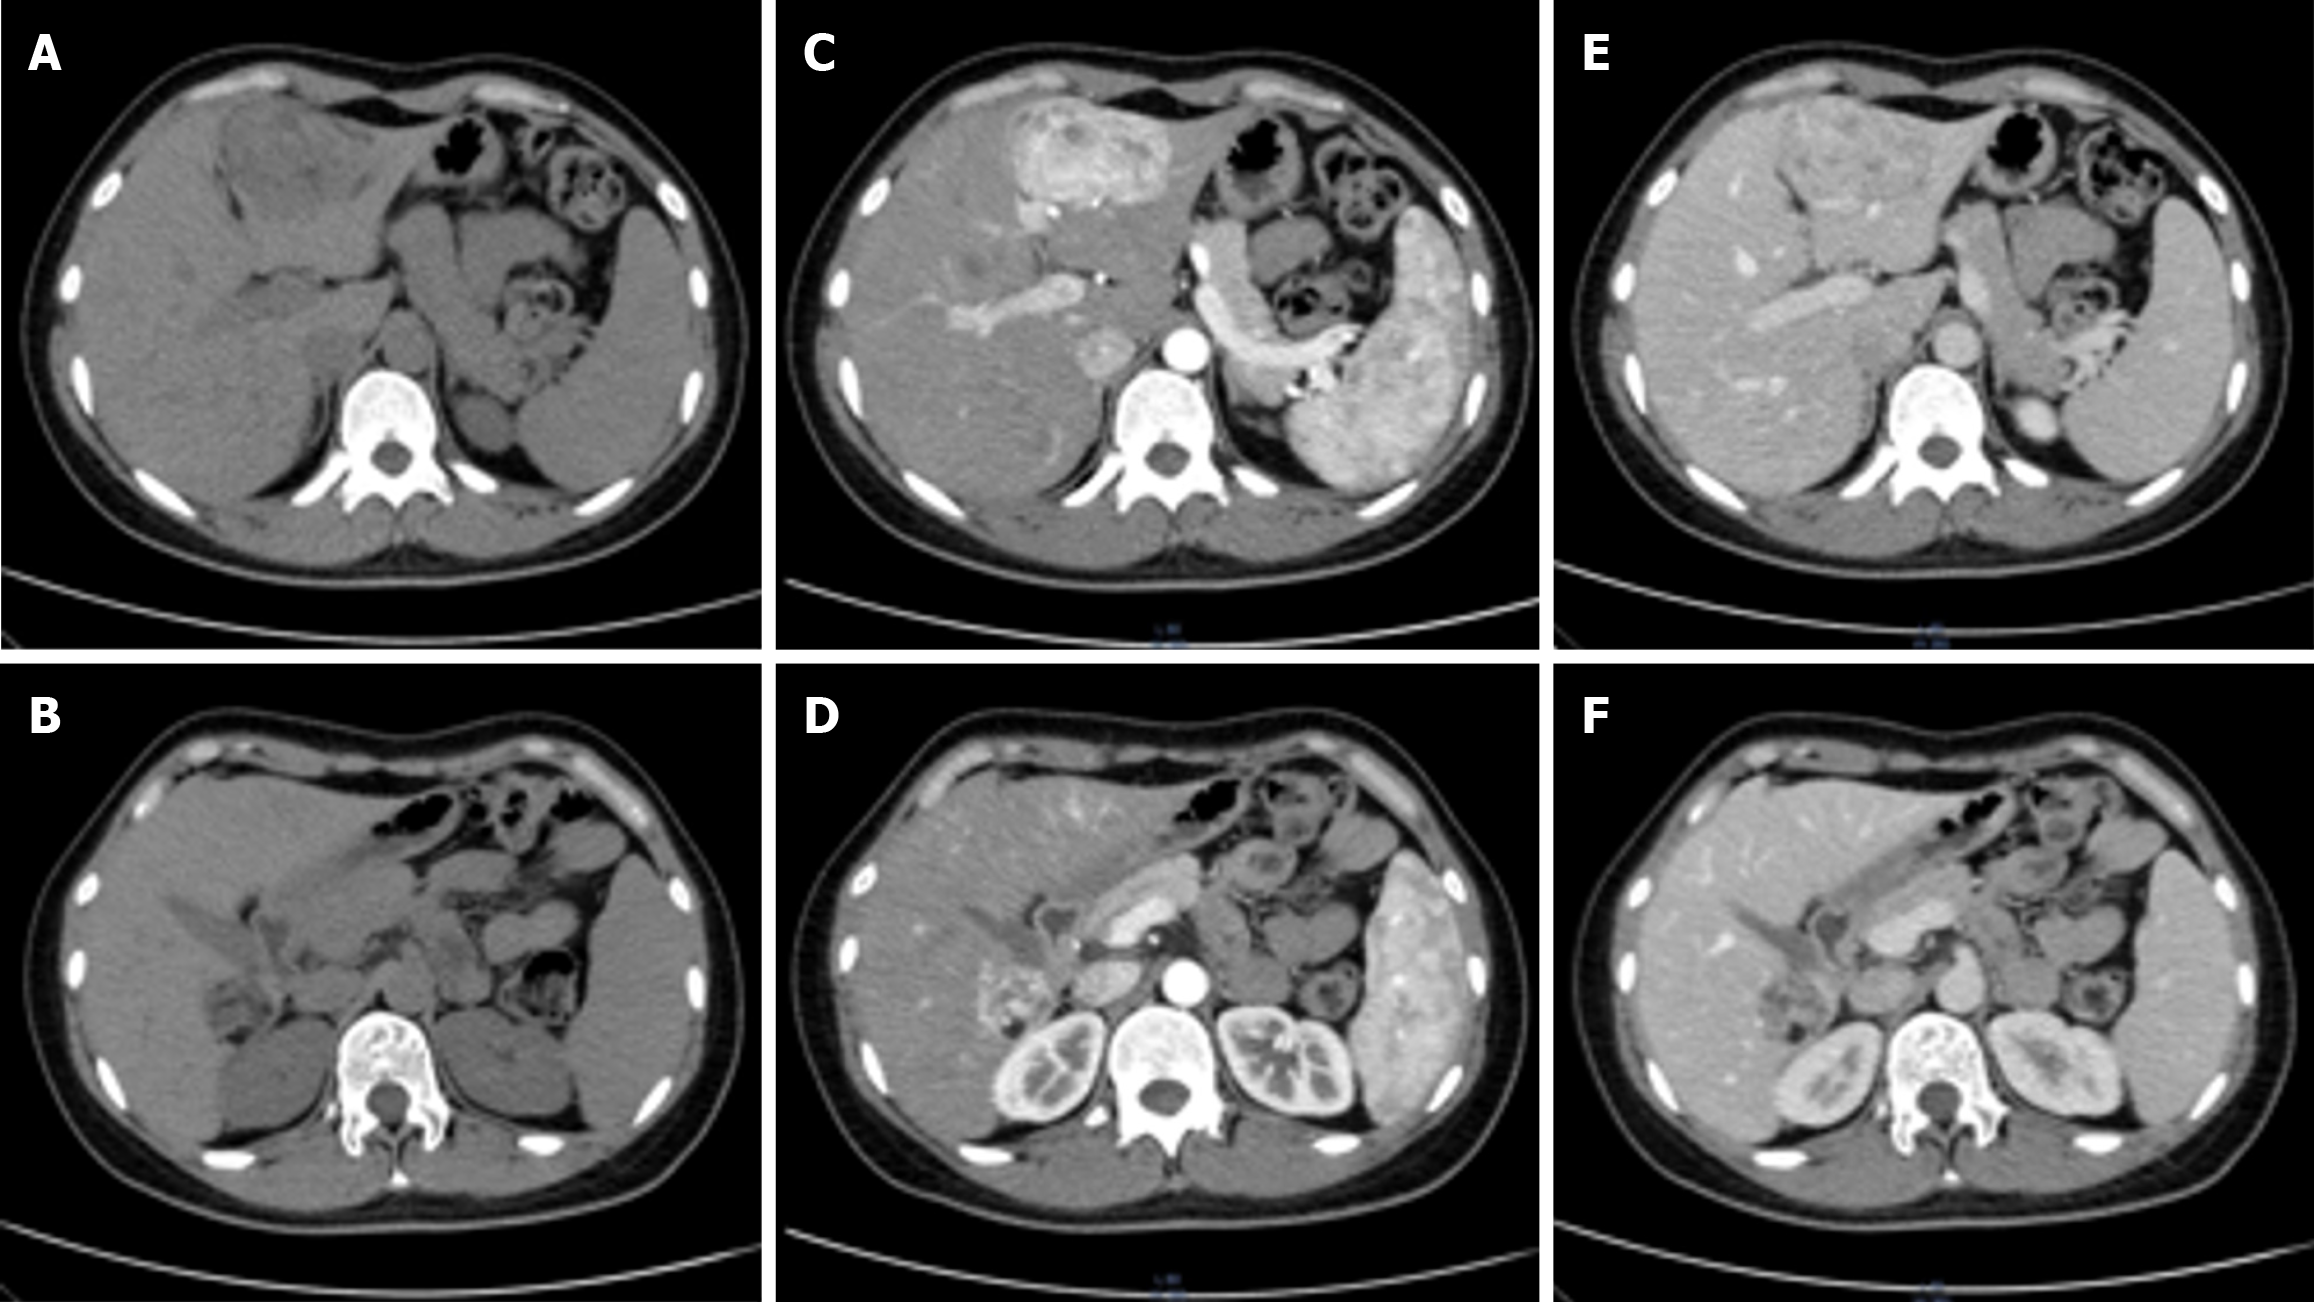

Ultrasound demonstrated a slightly hyperechoic lesion measuring approximately 71 mm × 49 mm in the left hepatic lobe and an additional lesion of approximately 33 mm × 32 mm in the right lobe, both with sharply defined margins. These sonogram findings were consistent with hepatic hemangiomas (Figure 1). Contrast-enhanced computed tomography (CT) of the upper abdomen revealed mass lesions in hepatic segments S3 and S7, with the larger one in the left lobe measuring approximately 61 mm × 44 mm and showing heterogeneous density. In the arterial phase, the lesion exhibited pronounced heterogeneous enhancement, with visible intratumoral vasculature and adjacent vessel dilation. The lesion became isodense during the portal venous and delayed phases. These radiologic findings were consistent with a possible diagnosis of AML (Figure 2).